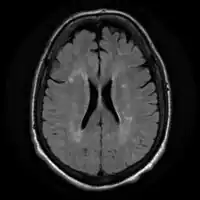

-

Acute severe hepatic encephalopathy -

Acute severe hepatic encephalopathy